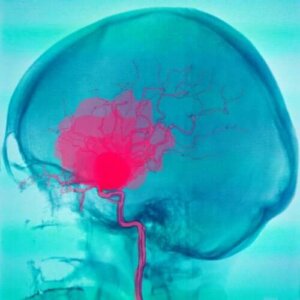

Hjernehinneblødning er når blodet samles mellom spindelvevshinnen og pia mater. Blodet kommer vanligvis fra arterier og det kan ha mange forskjellige årsaker. Det vanligste er en sprukket aneurisme. Det kan imidlertid også ha andre årsaker.